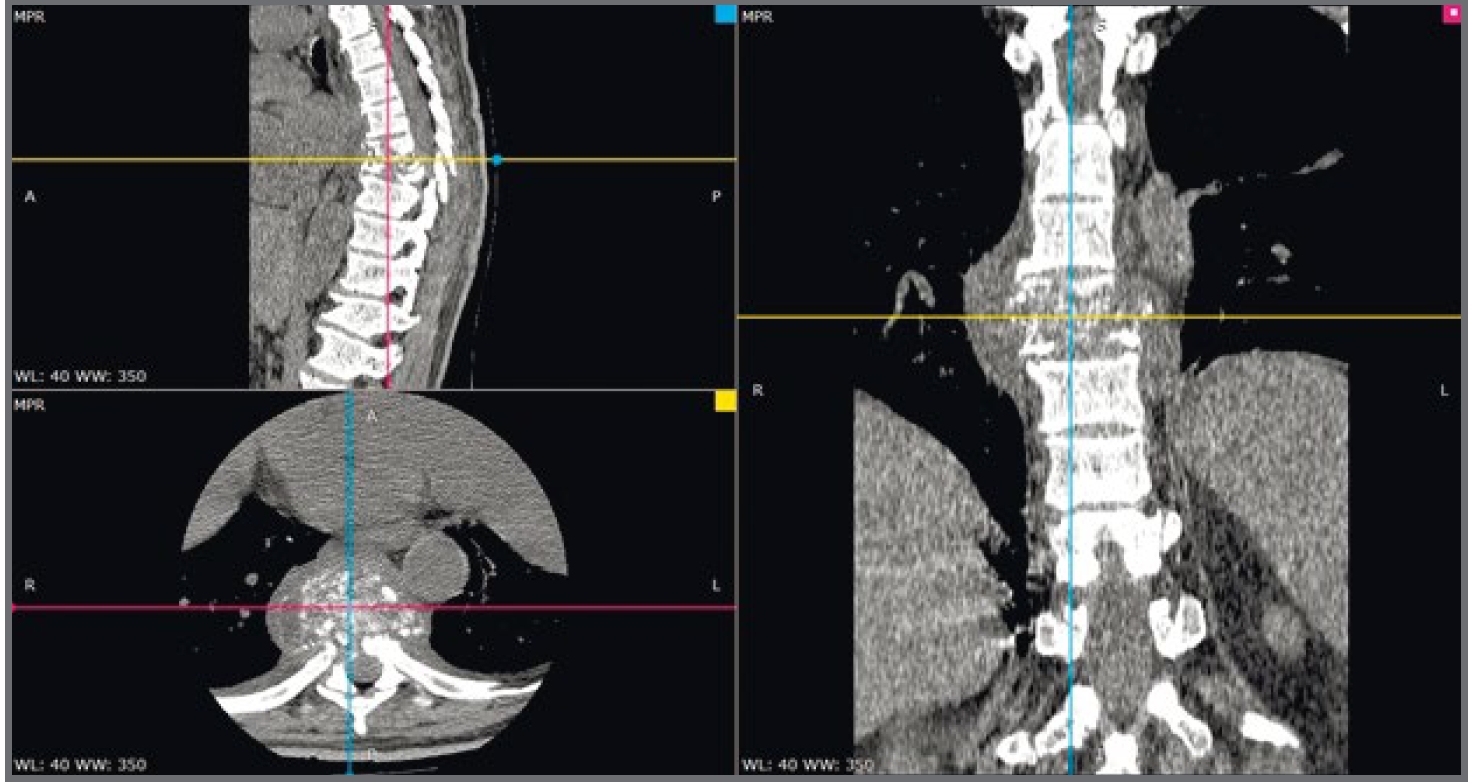

Выполнена ЭхоКС (13.03.2019), констатирован дискинез всех нижних, задне-боковых, верхушечного бокового сегментов левого желудочка (ЛЖ) с формированием ложной аневризмы; систоло-диастолический поток из ЛЖ в полость перикарда на границе базального и нижнего задне-боковых сегментов ЛЖ, ширина дефекта около 3–4 мм; объем аневризмы около 150 мл (5,5×8,0 см), объем жидкой части около 60 мл (4,5×5,0 см); тромб в проекции аневризмы (на уровне базальных сегментов ЛЖ) 4,5×5,0 см, средней эхогенности; снижение глобальной сократительной способности миокарда ЛЖ, фракция выброса 30% (рис. 2).

Рис. 2. ЭхоКС.

Fig. 2. EchoCS.